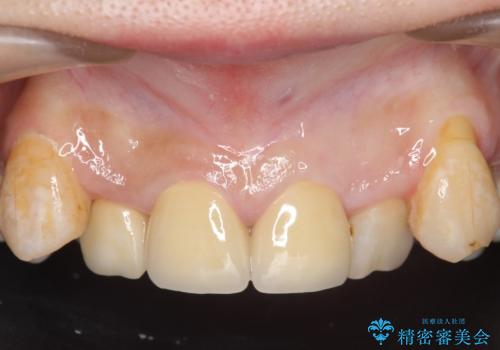

その後右上1,2番目及び左上1番目の歯に対してオールセラミッククラウンによる補綴を行いました。

今回用いたオールセラミッククラウンはジルコニアフレームという白い素材の上にセラミックを盛っているため、審美性が非常に高いのが特徴です。

また、ジルコニアは人工ダイヤモンドの材料にも使われているほど高い強度を持っており、そのためオールセラミッククラウンは審美性だけでなく、奥歯やブリッジの補綴も可能とするクラウンです。